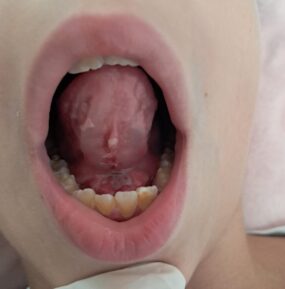

Skrócone wędzidełko języka

Skrócone wędzidełko języka może wpływać na sposób funkcjonowania języka oraz pracę całej jamy ustnej. Objawy bywają różne, dlatego ocena zawsze powinna uwzględniać wiek pacjenta i zgłaszane trudności. Istotna jest nie tylko sama budowa, ale również funkcja języka podczas codziennych czynności.

Nie każde wędzidełko, które wygląda na skrócone, powoduje trudności. Zdarza się również sytuacja odwrotna — budowa nie budzi dużych zastrzeżeń, a mimo to funkcja języka pozostaje ograniczona. Z tego powodu ocena powinna obejmować nie tylko wygląd, ale także sposób pracy języka w praktyce.

Dopiero połączenie obserwacji budowy i funkcji pozwala lepiej zrozumieć trudność. Dzięki temu łatwiej ocenić, czy skrócone wędzidełko rzeczywiście wpływa na codzienne funkcjonowanie. Co więcej, taka analiza pomaga dobrać odpowiednie wsparcie.